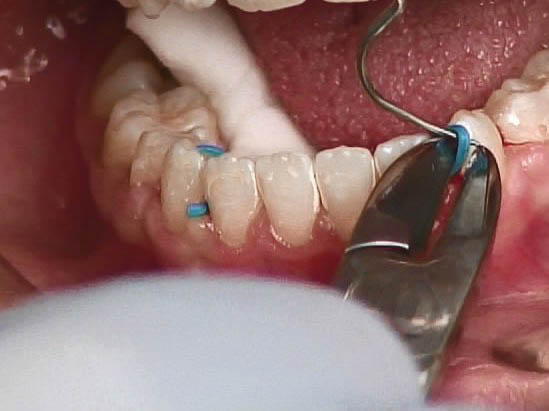

سیم را روی سینگلوم قرار دهید. اگر درون حفره دهان نیاُفتاد که مشغول چسباندن آن میشوید. اگر روی سینگلوم قرار نمیگیرد باید دو عدد سپراتور پلاستیکی بین دندانهای 2و3 دو طرف قرار دهید و سیم را از زیر آن رد کنید تا محکم به سینگلوم بچسبد (شکل 71-4). میتوانید دو سه قطعه نخ دندان بردارید و هرکدام را از کنتاکت بین دندانها رد کنید و سیم را بگذارید روی آن و بعد نخها را گره بزنید تا سیم در محل خود محکم شود.

ابتدا سطح سینگلوم دندانها را با پودر اکسید آلومینیوم 50 میکرون سندبلاست کنید و سپس با اسید اچ و رزین سطح سینگلوم را آماده میکنید. رزین را اشعه بدهید تا کیور شود و بعد با کامپوزیت ارتودنسی سیم را به دندان متصل نمایید. خیلی مراقب باشید تا سطح دندان با بزاق آلوده نشود. بعد از کیور شدن برای خارج کردن سپراتور میتوانید آن را با نوک سوند از روی دندان بلند کنید و با قیچی یا کاتر آن را قطع کنید (شکل 72-4) و سپراتور را از لای امبراژور دندان خارج کنید.

شکل 71-4: قراردادن سیم Twisted به کمک سپراتور